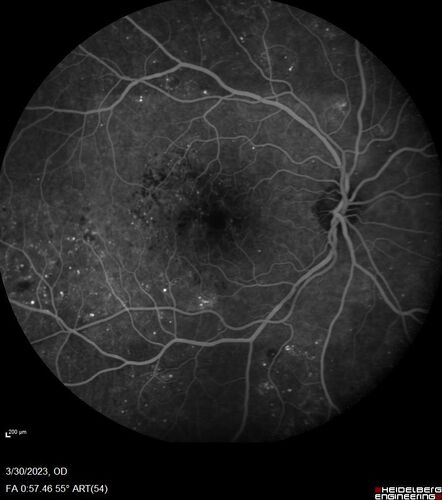

Macular ischemia left eye in type I diabetic (enlarged foveal avascular zone)

29 year old female with type I diabetes since age 5. Left eye has enlarged FAZ with vision of 20/20 OD and 20/60 OS. Both eyes have CSME. The left eye did have focal laser